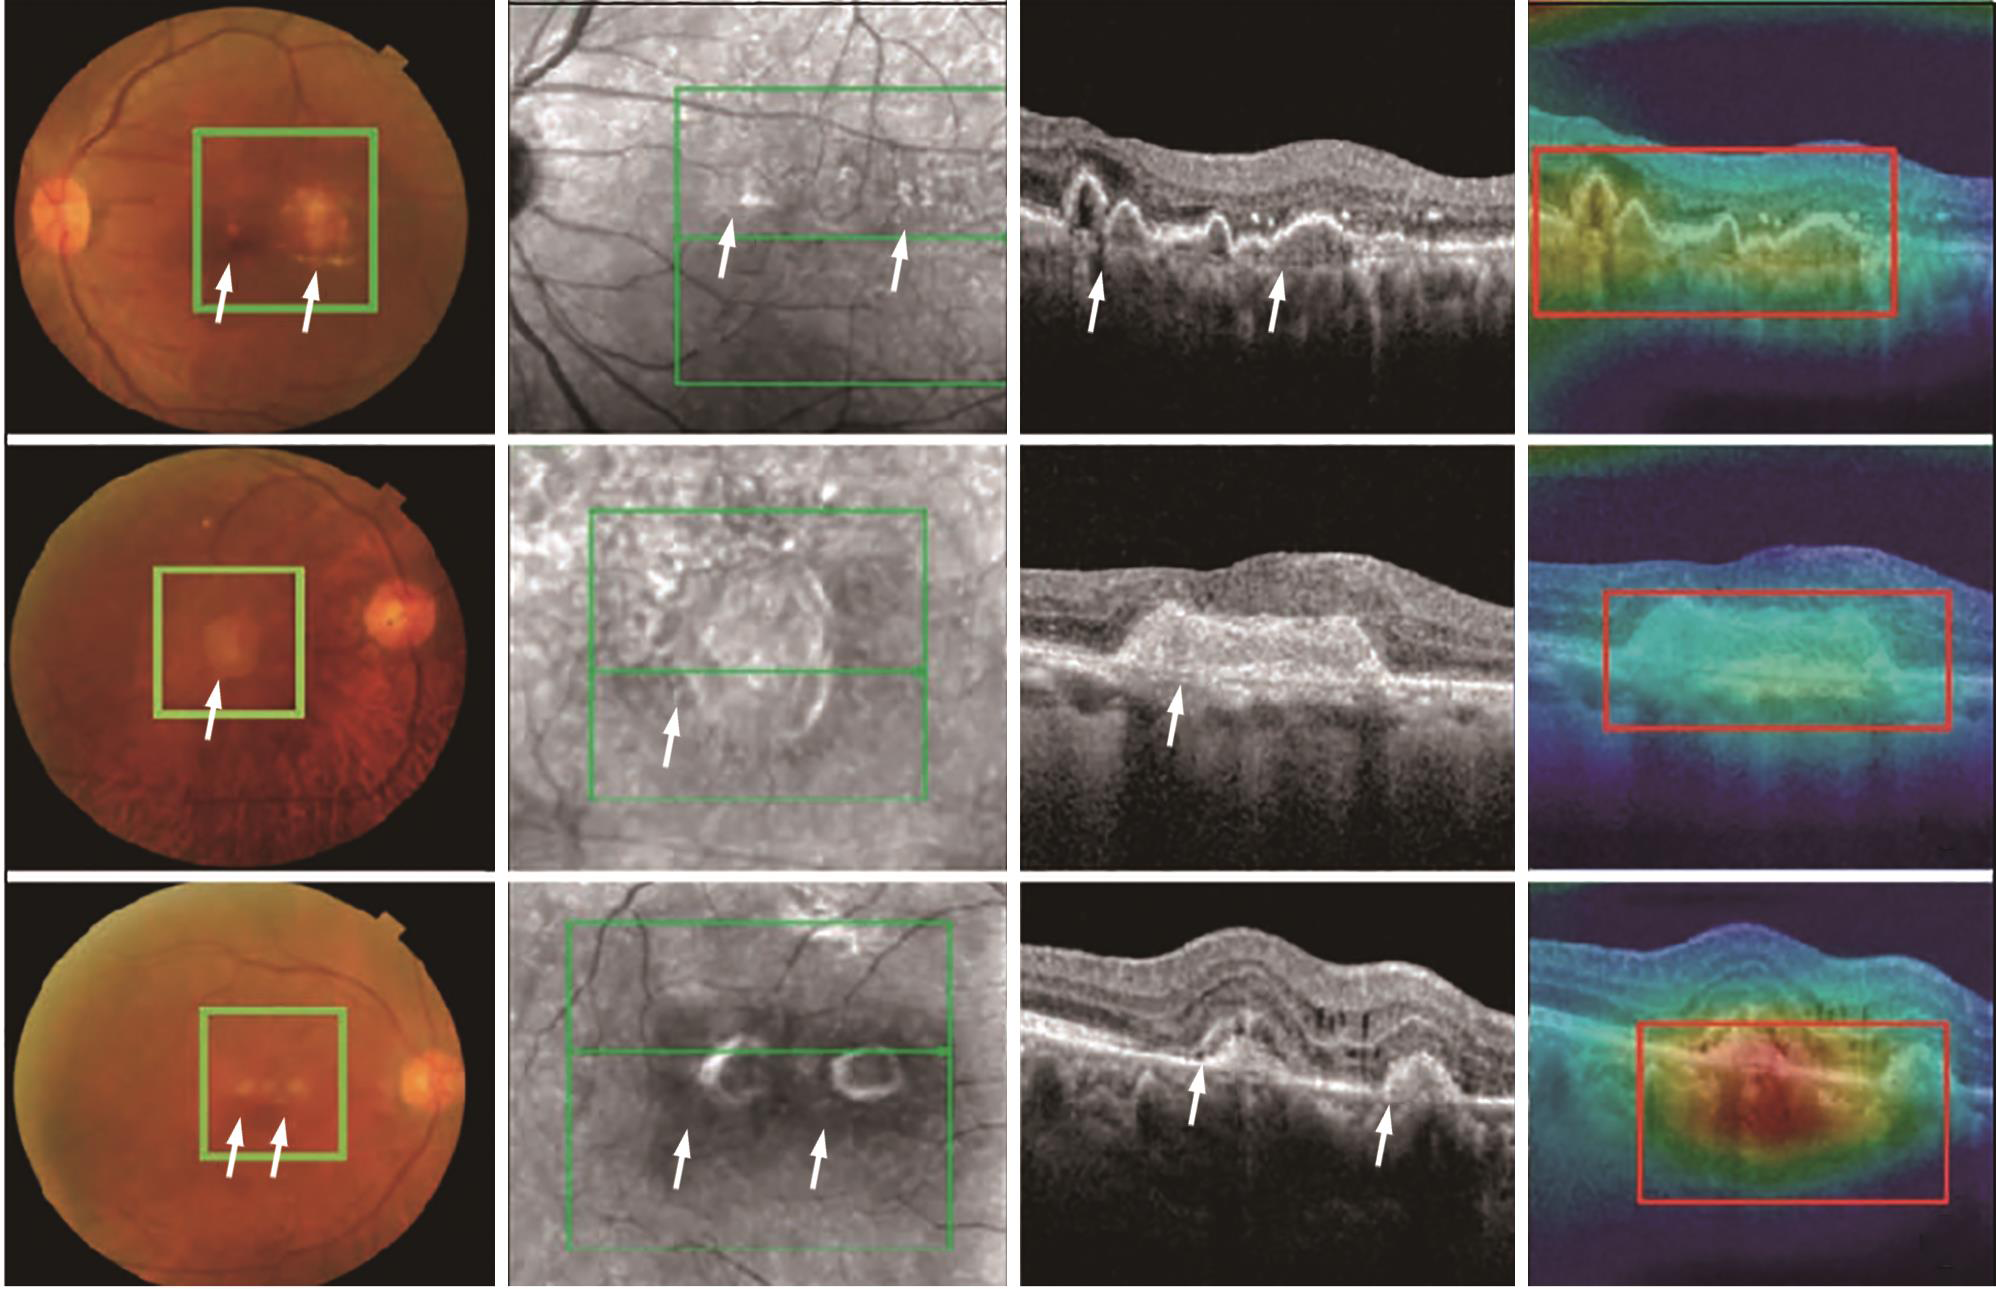

2. AMD的筛查:Burlina等[16]使用超过13万张眼底彩照建立深度卷积网络,识别是否患AMD准确率90%,提示应用深度学习的AMD自动评估模型能够筛选出需要就医的患者。OCT可以识别眼底照中不可见的早期地图样萎缩标志性的高反射灶和视网膜外层变薄(萎缩);因此,OCT较彩色图像对AMD筛查的效果更佳。然而,由于人工与时间成本过高,OCT难以被应用于大规模筛查。龚雁等[17]采用基于弱监督学习的深度学习算法,将ResNet-101深度模型应用于OCT图像的AMD分类中,诊断准确率94.9%,优于CNN-AlexNet、VGG及Google-Net(分别为85.3%、88.7%、89.2%);该模型能够精准定位病灶区域(图1),且相较传统监督学习算法减少了时间精力;提示通过大样本的研究与训练,低成本的基于OCT的AMD筛查普及将成为现实。